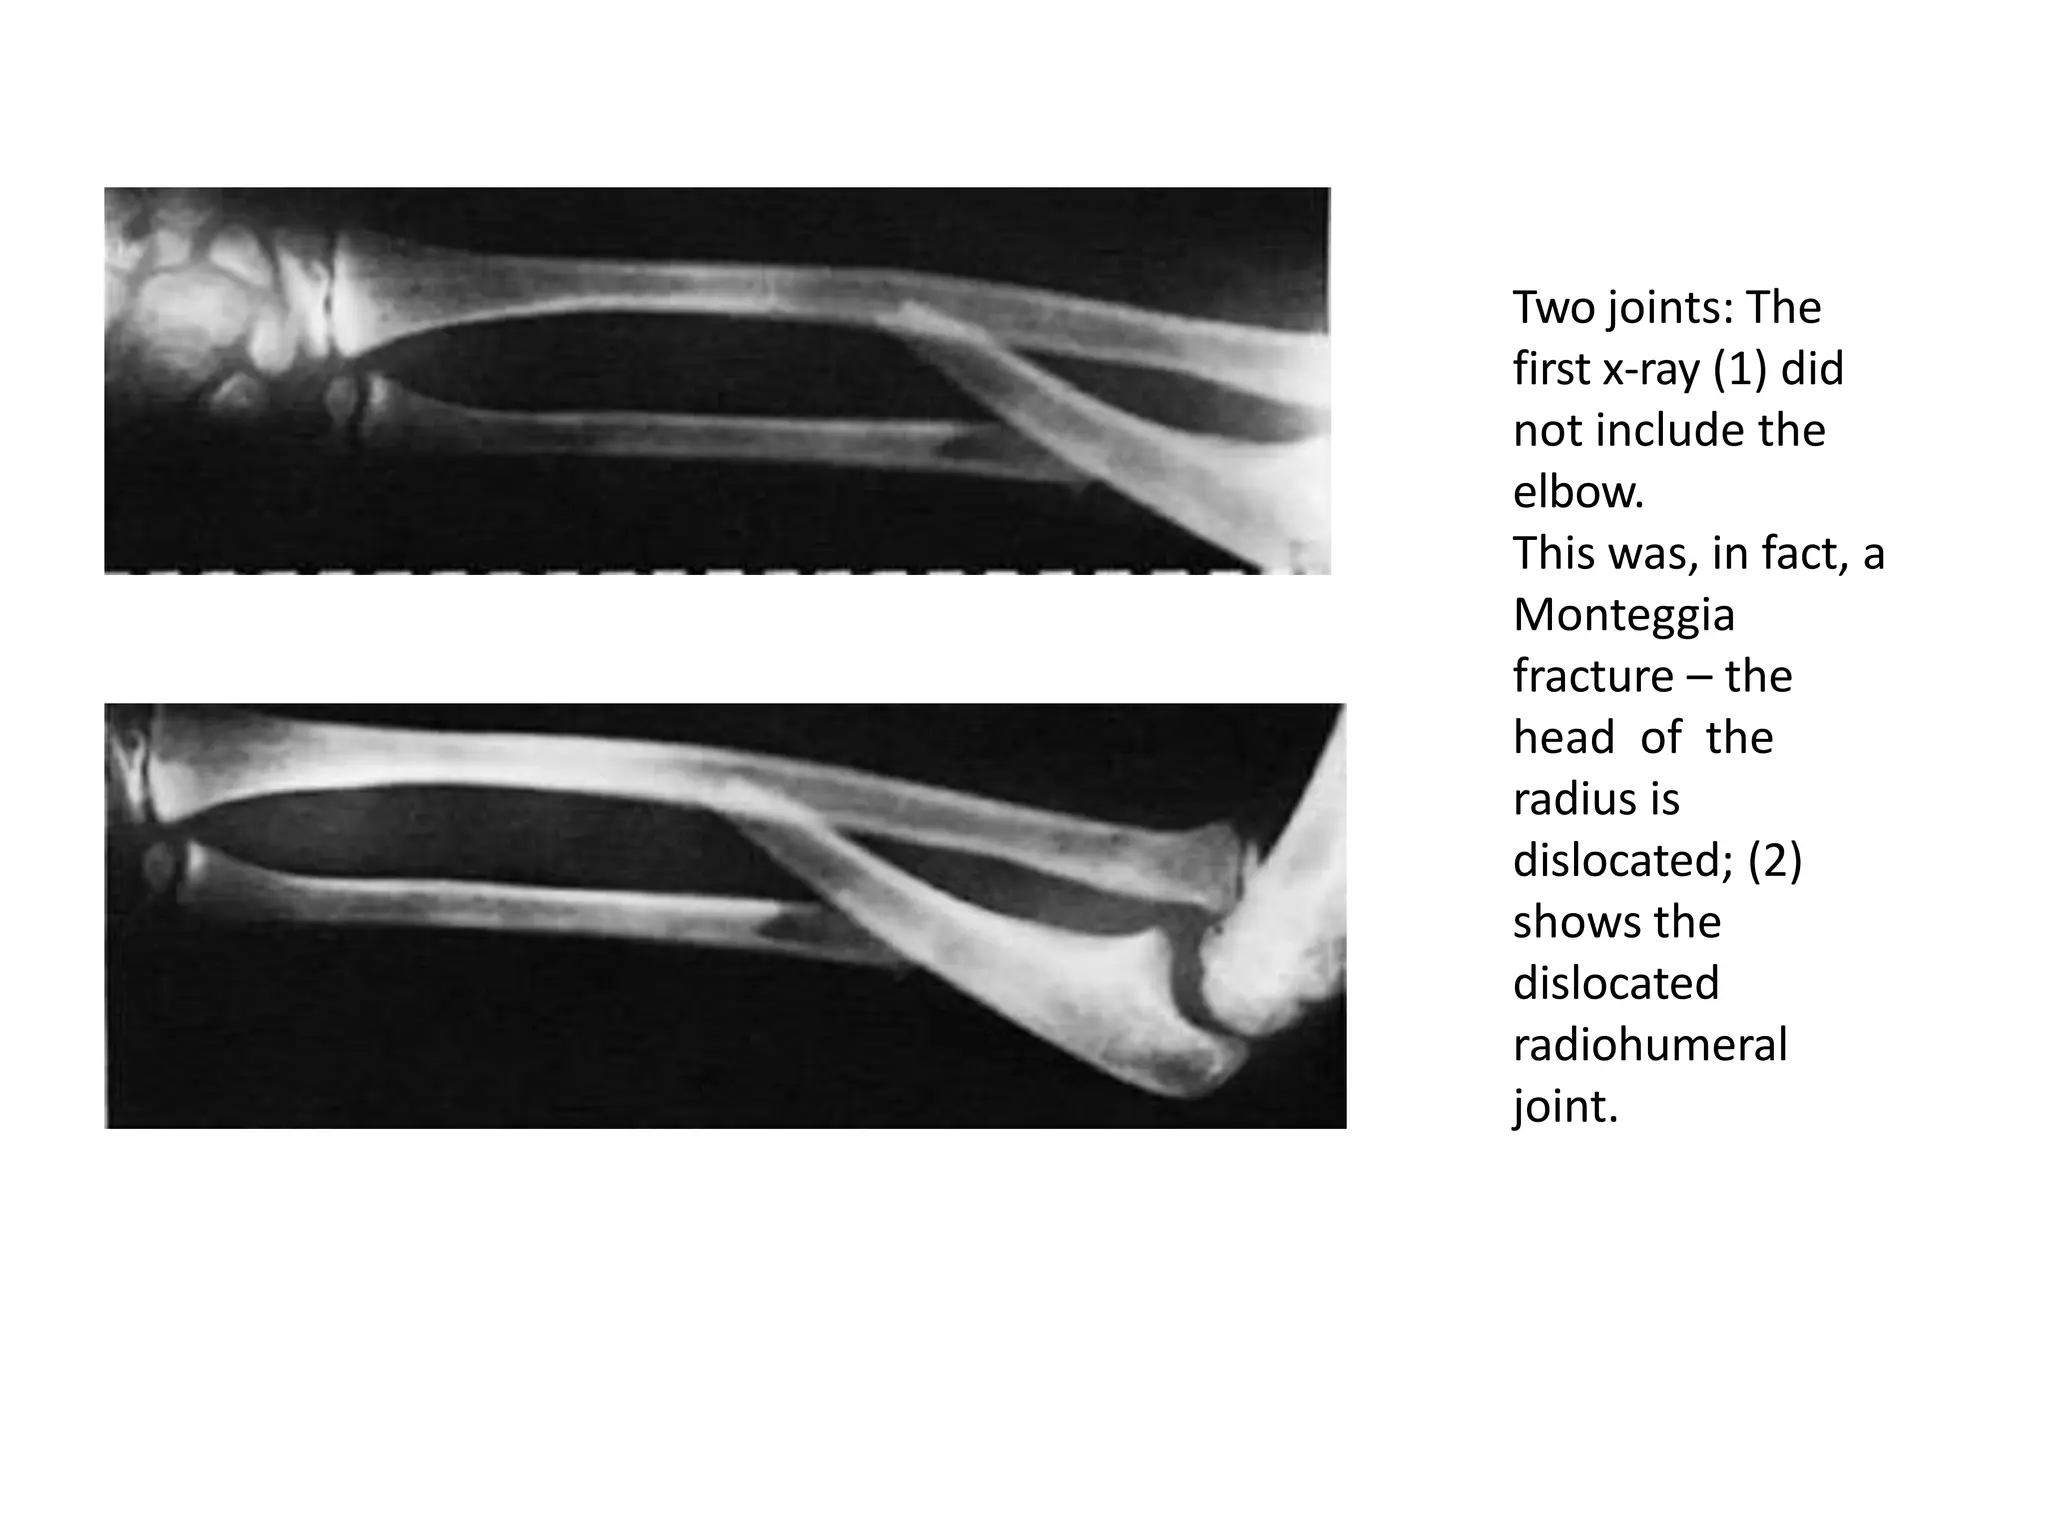

Two joints – In the forearm or leg, one bone may be fractured

and angulated. Angulation, however, is impossible unless the

other bone is also broken, or a joint dislocated. The joints

above and below the fracture must both be included on the x-

ray films.

Two joints: The

first x-ray (1) did

not include the

elbow.

This was, in fact, a

Monteggia

fracture – the

head of the

radius is

dislocated; (2)

shows the

dislocated

radiohumeral

joint.

Two joints: The firstx-ray (1) did not include the elbow. This was, in fact, a Monteggia fracture – the head of the radius is dislocated; (2) shows the dislocated radiohumeral joint.